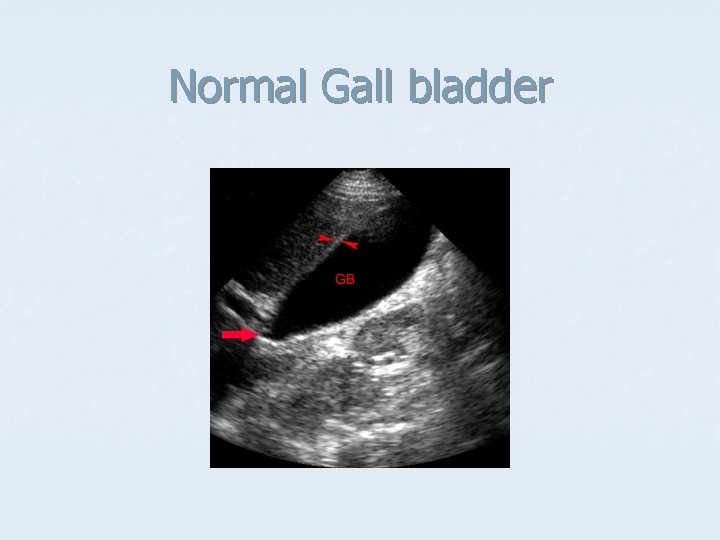

Normal Gall bladder